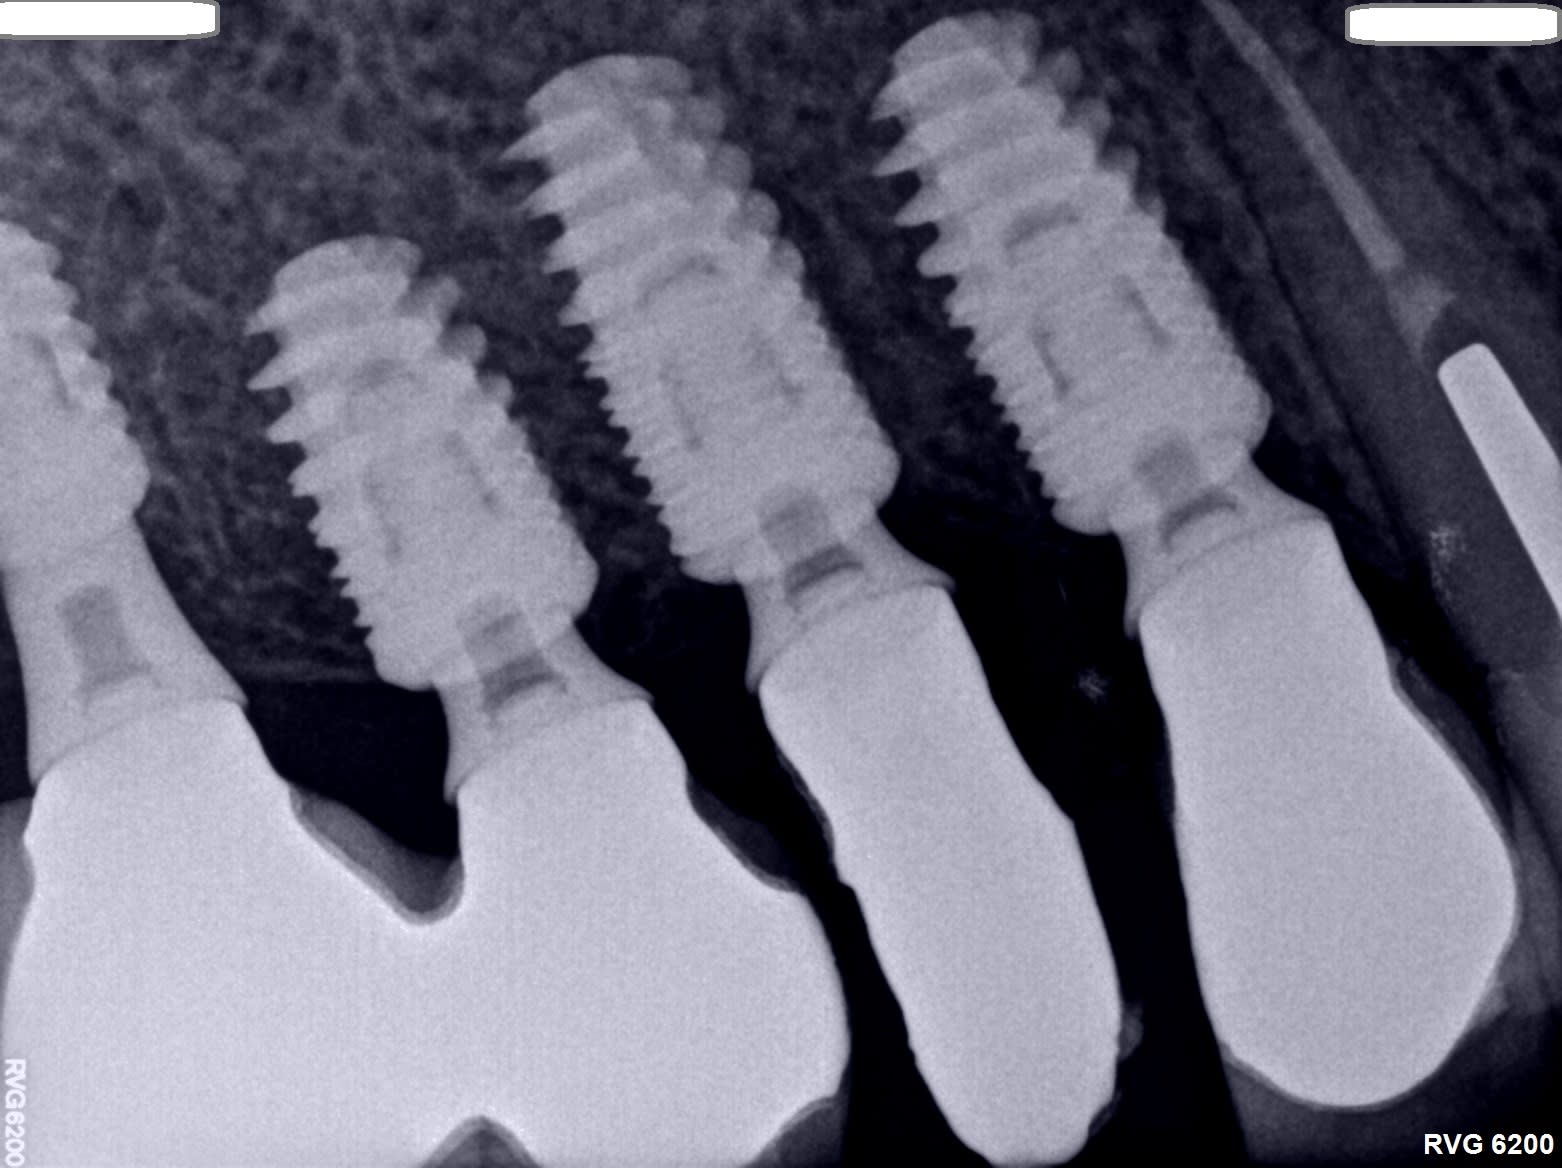

Les éléments de 14 à 17 sont solidarisés et naturellement , la céramique a fracturé sur 15 . J'ai donc coupé en mésial et distal pour reprendre L'empreinte pensant pouvoir dévisser le pilier.

Aucun de mes embouts fonctionne ( Astra, Anthogyr, Nobel..) donc avez-vous une idée de la marque ? ( Ankylos ? )

J'ai l'impression que ce sont des AXIOM

En bas oui, un reg et un PX….mais pour le haut le col semble différent….donc rétro pour ne pas dire de bêtises

En haut c’est plus un implant genre interactive ID, ou Keystone genesis, etc….ou même genre quatro blue skybio….mais la pano ne me donne pas assez de détails pour sortir une identification fiable

Ci-joint la rétro. En effet, j'ai bien posé des Anthogyr en bas. On distingue les découpes . Si non identifié : je retaille et empreinte conjointe classique mais à regret.